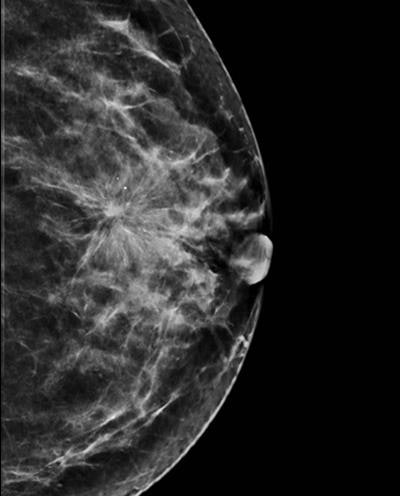

The strength of the national screening program lies in the fact that it is decentralized, meaning it can take place locally -- in any of the 2,700 centers across France that provide mammography -- and can be tailored to the patient, according to Ceugnart, who is head of imaging at the Oscar Lambret Centre in Lille. Ultrasound is offered systematically to patients with dense breasts, and it is performed at the same screening consultation by a radiologist, rather than in a follow-up appointment.

In the case of anomalies, radiologists may perform a diagnostic DBT exam, which, so far, is not authorized for systematic screening purposes in the healthy population due to further irradiation on top of the amount received from standard mammography.

Presenting an outline of the review at the recent national congress, JFR 2019, Ceugnart noted that combining mammography and DBT seemed to yield better detection rates than mammography alone. However, complementary studies are needed to obtain more robust results, particularly in terms of interval cancer rates. He also pointed to the possibility of synthesized images generated from DBT datasets to avoid additional radiation exposure.

For example, the Adjunct Screening With Tomosynthesis or Ultrasound in Women With Mammography-Negative Dense Breasts (ASTOUND) study showed that ultrasound has better incremental breast cancer detection than DBT in mammography-negative dense breasts at a similar false-positive recall rate. However, DBT detected more than 50% of the additional breast cancers in these women, according to the authors.